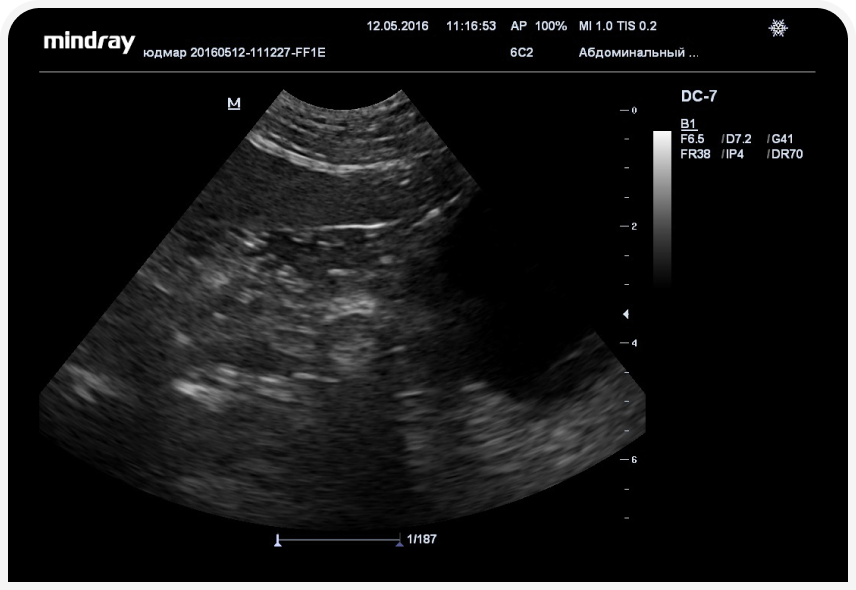

УЗИ-диагностика может выявить спленомегалию и признаки острого нефрита с канальцевым некрозом почек (Фото 2).

Острый нефрит с тубулярным некрозом при отравлении луком и чесноком встречается редко, он связан с выведением с мочой большого количества гемоглобина или метгемоглобина. УЗИ-признаки острого тубулярного некроза (повышение индекса резистентности выше 0,8) свидетельствуют о серьезных, иногда необратимых повреждениях ткани почек и ухудшают прогноз.